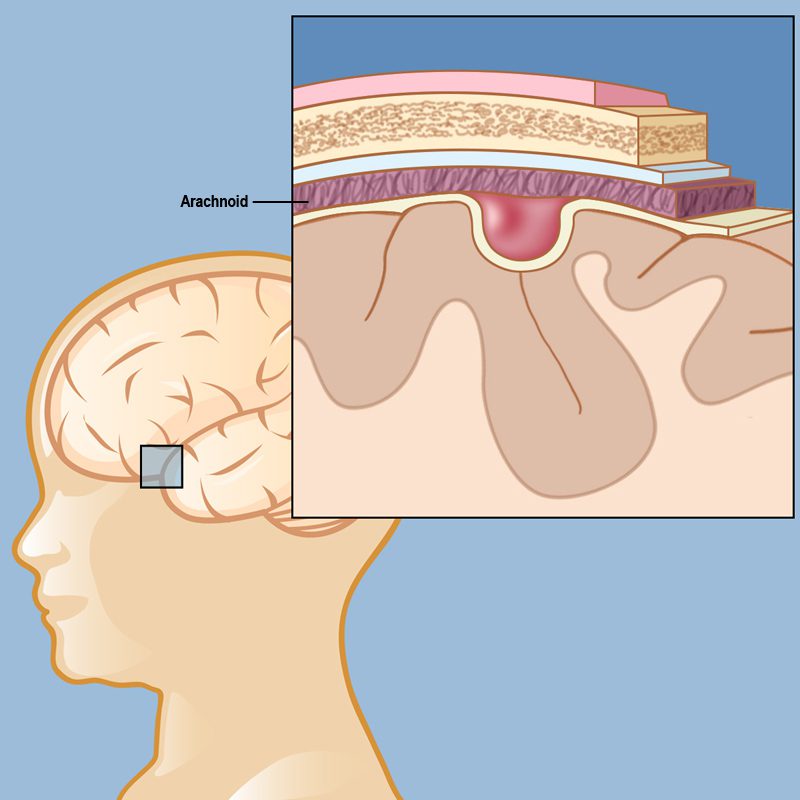

الكيس العنكبوتي عبارة عن أكياس مملوءة بالسوائل تتكون بين أوراق الغشاء العنكبوتي من الأغشية المحيطة بالدماغ والحبل الشوكي. يحتوي الدماغ على أغشية من الخارج إلى الداخل تسمى الأم الجافية والعنكبوتية والأم الحنون. على الرغم من وجود الكيسات العنكبوتية في العنكبوتية، فإنها عادة ما تتمدد إلى الداخل. المكان الأكثر شيوعًا لتواجدها هو بالقرب من الفص الصدغي للدماغ. يمكن رؤيتها أيضًا في البطين الثالث، والمنطقة فوق السرج التركي، والمخيخ، وجذع الدماغ. السبب الحقيقي لحدوثه غير معروف. نادرًا ما يتطور الكيس العنكبوتي بسبب الصدمة أو الورم أو العدوى أو جراحة الأعصاب.

الكيس العنكبوتي هو أكثر أنواع كيسات الدماغ شيوعًا ويحدث بسبب تراكم السائل النخاعي. لا تعتبر هذه الأكياس ورما دماغيا. تتشكل الأكياس العنكبوتية بين الدماغ أو النخاع الشوكي والغشاء العنكبوتي. عادة ما تكون هذه الأكياس موجودة عند الولادة ولكنها تحدث أحيانًا نتيجة إصابة في الرأس أو جراحة أو التهاب في الرأس وما إلى ذلك.